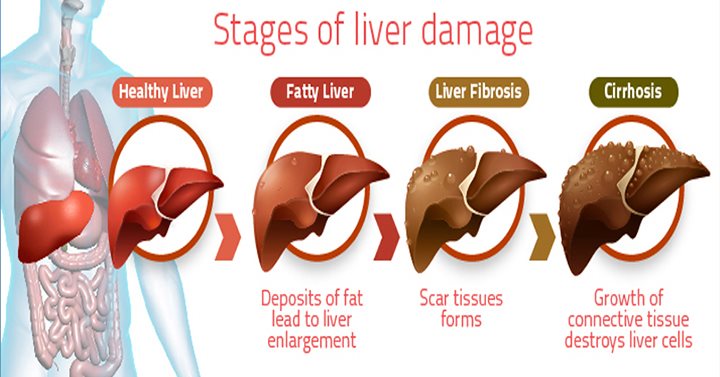

Liver cirrhosis is a progressive condition where scar tissue replaces the healthy tissue of your liver, which eventually results in your liver’s inability to function properly. This happens because the scar tissue prevents the flow of blood through the liver and slows the processing of nutrients, hormone, drugs, and...